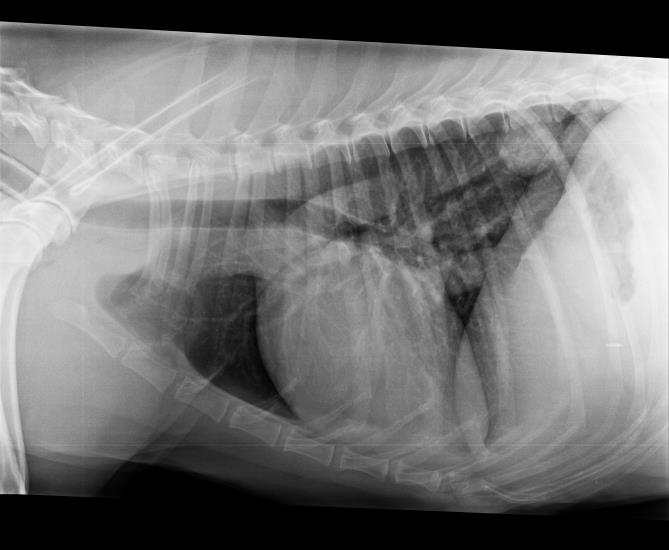

Conventional three-view radiography (i.e. left and right lateral and DV/VD projections) is usually enough to

detect a pulmonary mass. Clinicians should pay particular attention to assessing radiographs for potential masses in areas of overlapping soft tissue densities i.e. overlying the heart and diaphragm as smaller lesions can be missed. Larger, peripheral masses can be further assessed with ultrasound and guided fine-needle aspirates can be taken if desired but this is not without risk of creating pneumothorax or intrapulmonary haemorrhage/haemoptysis.

Figure 1: Lateral thoracic radiograph showing typical appearance of a peripheral pulmonary mass within the caudodorsal thorax

Fig 1: Lateral thoracic radiograph showing typical appearance of a peripheral pulmonary mass within the caudodorsal thorax.